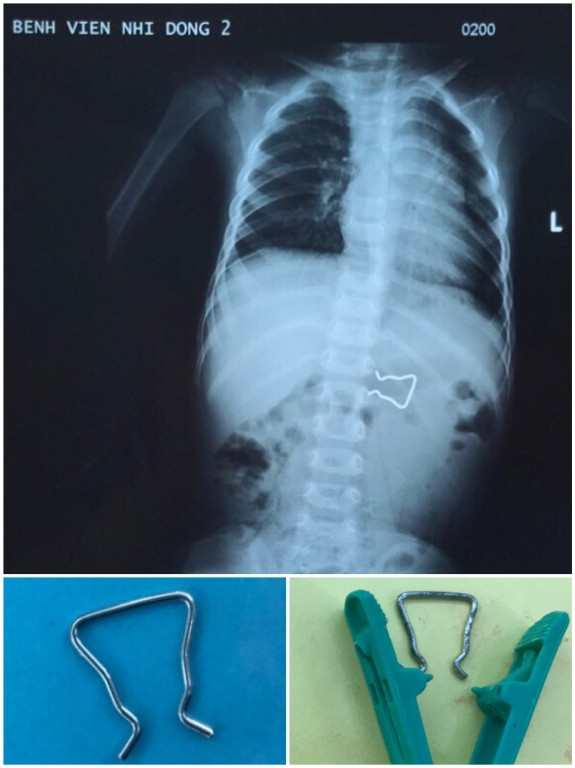

Theo đó, bé trai được chuyển viện từ BV tỉnh Đắk  Lắk  sau khi nuốt phải dị vật. Kết quả X-quang cho thấy dị vật là chiếc móc sắt dùng để cố định trong kẹp quần áo. Theo lời kể của người nhà, có thể chiếc móc sắt này đã bị rớt ra ngoài, không may bé trai nhặt và cho vào miệng nuốt.

Nuốt móc sắt kẹp quần áo, bé trai 18 tháng suýt thủng ruột ảnh 2Chiếc móc sắt với 2 cạnh bên sắt  nhọn